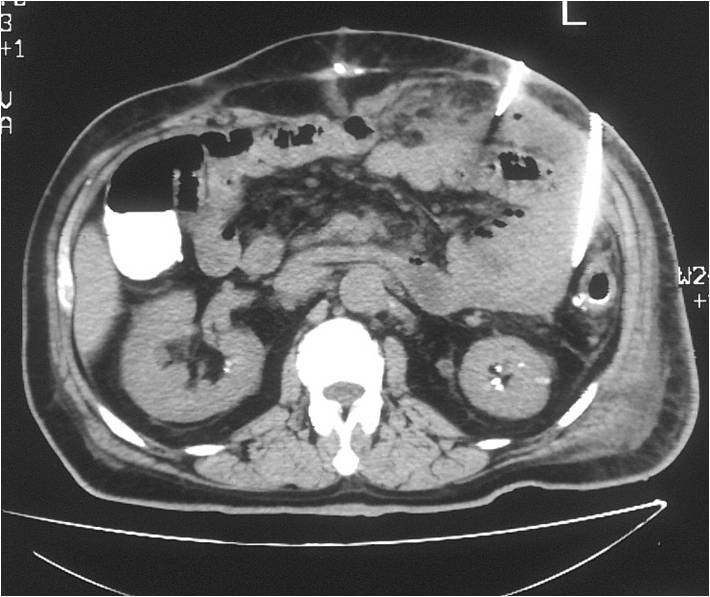

- Abscess post right hemicolectomy

- Successful placement and drainage